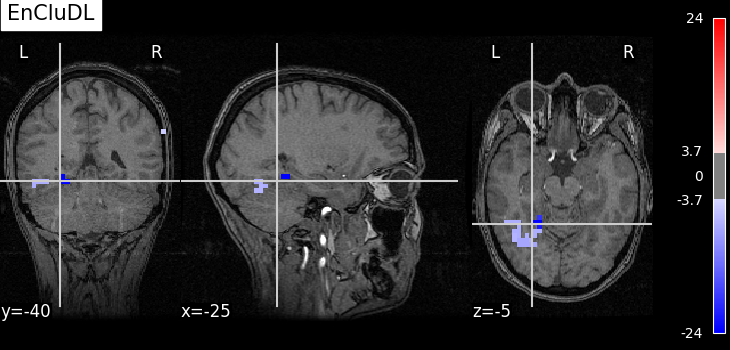

selected_encludl = encludl.fwer_selection(fwer=target_fwer, two_tailed_test=True)

z_score_encludl = zscore_from_pval(encludl.pvalues_) * selected_encludl

plot_map(

z_score_encludl,

float(zscore_from_pval(target_fwer / 2 / n_clusters)),

"EnCluDL",

)

As advocated in introduction, the methods that do not reduce the original problem are not satisfying since they are too conservative. Among those methods, the only one that makes discoveries is the one that threshold the SVR decoder using a parametric approximation. However this method has no statistical guarantees and we can see that some isolated voxels are discovered, which seems quite spurious. The discriminative pattern derived from the clustered inference algorithm (CluDL) show that the method is less conservative. However, some reasonable patterns are also included in this solution. Finally, the solution provided by the ensemble clustered inference algorithm (EnCluDL) seems realistic as we recover the visual cortex and do not make spurious discoveries.